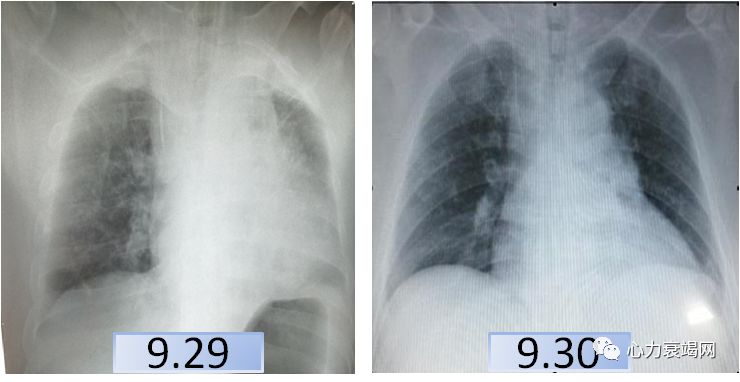

(ECMO第2天,9.30)

心功能较前变化不大

心功能较前明显好转,EF50%

课件提供资料:本例患者以压榨性胸痛发作3天于9月29日转入,入院时Bp 84/46mmHg,心电图示S1QⅢTⅢ、V5导联R/S<1,cTnT 0.144ng/ml,NT-pro-BNP6177.7 pg/ml,D二聚体11.68mg/L,Lac 7.7mmol/L,入院考虑冠心病心梗,肺栓塞?肺癌?初步治疗后(不详)胸闷胸痛无好转,血压持续低,心电不稳定,PaQ2降至87mmHg,PaCO2及乳酸升高,即予ECMO、液体负平衡、抗凝抗血小板并加予”左西孟旦”治疗,逐渐血压上升,氧合改善,一周后转普通病房治疗,10月9日又突发胸闷气短,后续治疗未列出。入院前淋巴结活检提示:转移性低分化腺癌,CTPA示肺栓塞。